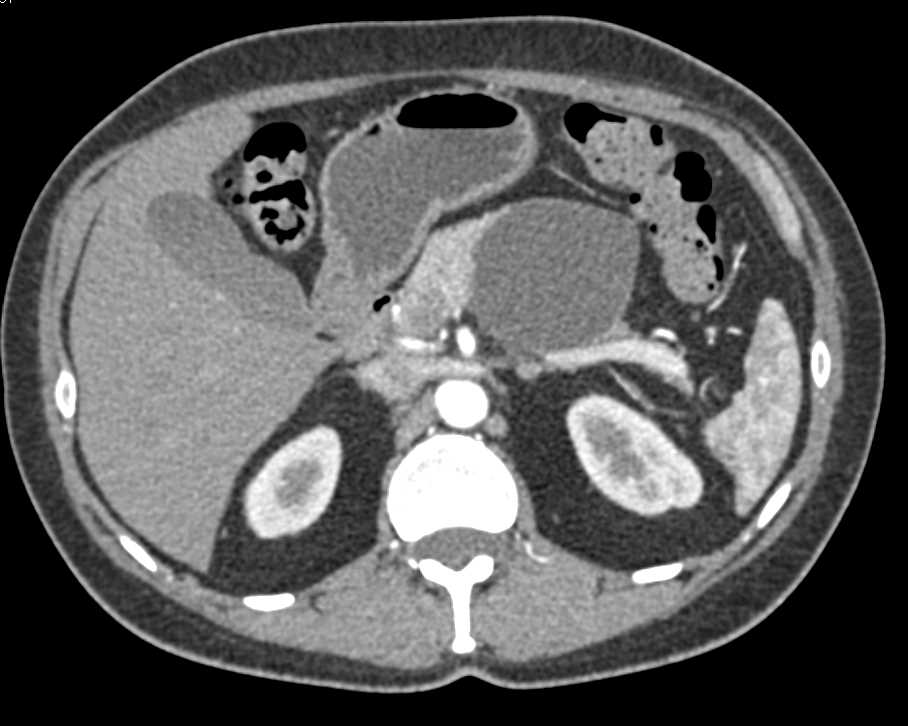

Pancreatic Cancer Encases the Celiac Artery and Narrows It